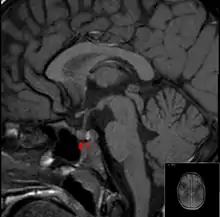

Diagnosis

It is recommended that magnetic resonance imaging (MRI) scan of the pituitary gland is performed if the diagnosis is suspected; this has a sensitivity of over 90% for detecting pituitary apoplexy; it may demonstrate infarction (tissue damage due to a decreased blood supply) or hemorrhage.[1] Different MRI sequences can be used to establish when the apoplexy occurred, and the predominant form of damage (hemorrhage or infarction).[2] If MRI is not suitable (e.g. due to claustrophobia or the presence of metal-containing implants), a computed tomography (CT) scan may demonstrate abnormalities in the pituitary gland, although it is less reliable.[1] Many pituitary tumors (25%) are found to have areas of hemorrhagic infarction on MRI scans, but apoplexy is not said to exist unless it is accompanied by symptoms.[1][4]